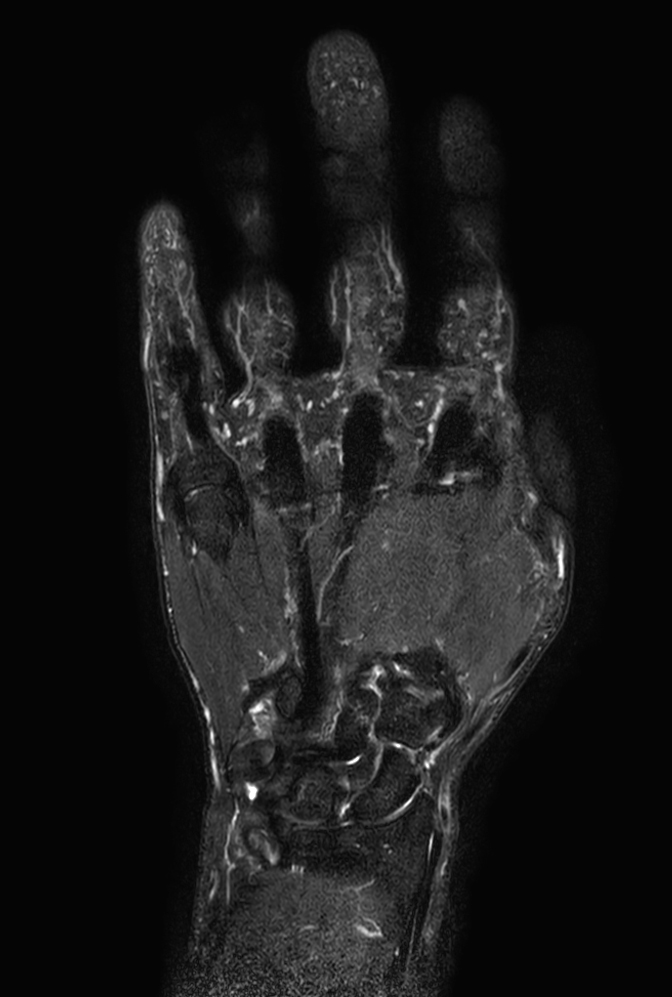

Coronal STIR TSE